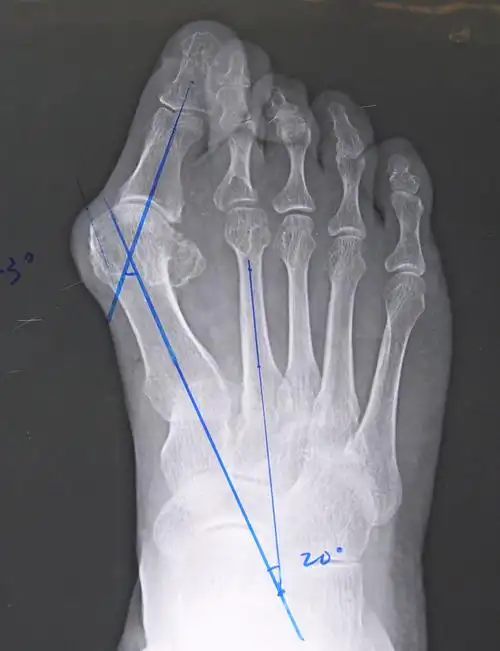

大脚骨scarf akin截骨 - 好大夫在线

拇趾向外偏斜,拇趾近节趾骨与第1跖骨成角大于15°,有"大脚骨","大觚